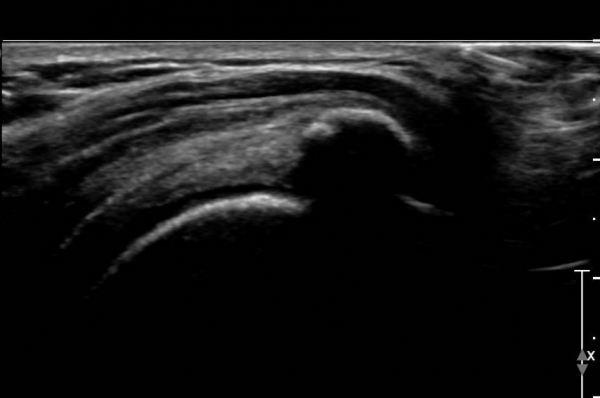

ÃÊÀ½ÆÄ °Ë»ç :  ¿À±¸µ¹±â °ßºÀÀδë Á¾´Ü¸é°Ë»ç¿¡¼­ ÀÎ´ë ½ÉÃþ¿¡ ¼ö¾×Àú·ù°¡ °üÂûµÇ´Âµ¥(»çÁø 1) ÀÌ °ÍÀº

¸¸¼ºÀûÀÎ Ãæµ¹ÁõÈıºÀ» ¾Ï½ÃÇÑ´Ù.